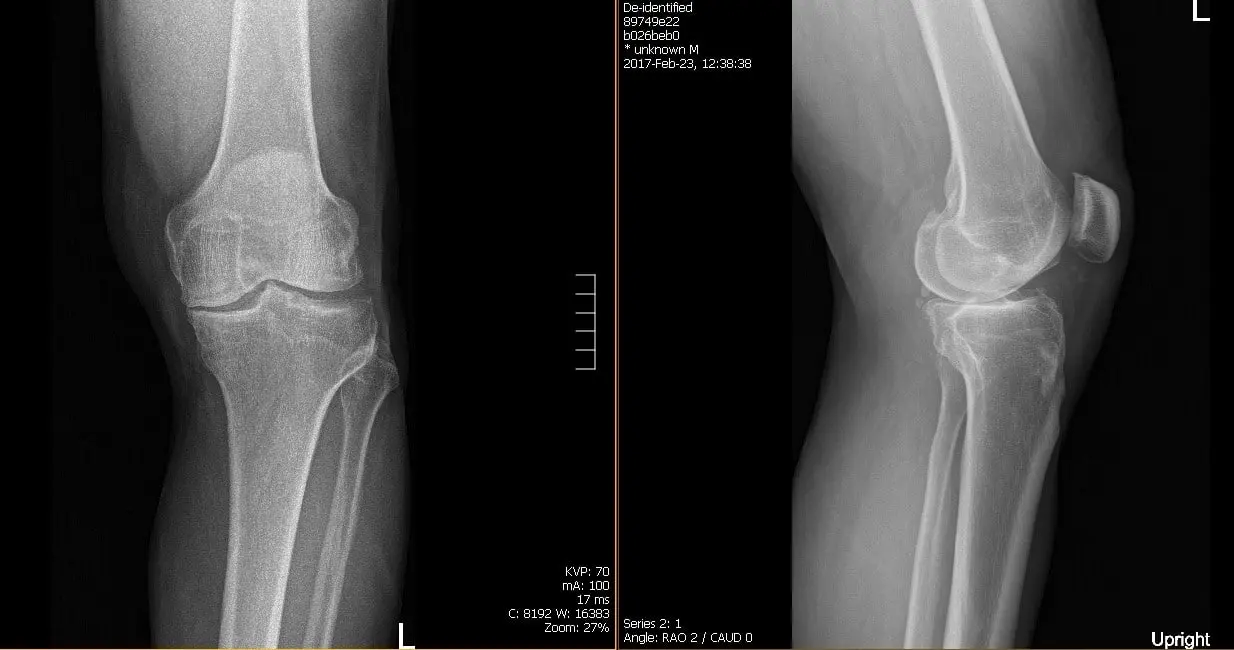

His HEP consisted of quadricep isometric, hamstring, and gluteal exercises, a seated knee flexion stretch and a supine knee hang. Patient was instructed to continue his HEP in addition to the new HEP program that would be given to him in outpatient PT. Presurgical films revealed there are moderate osteoarthritic degenerative changes.

Patient underwent a Left Total Knee Arthroplasty using custom implant, During the procedure his surgeon noted advanced osteoarthritis was already present. A medial parapatellar approach was used, the tibial resection guide was then placed into position after exposure of the tibia, and the tibial resection was made and checked.